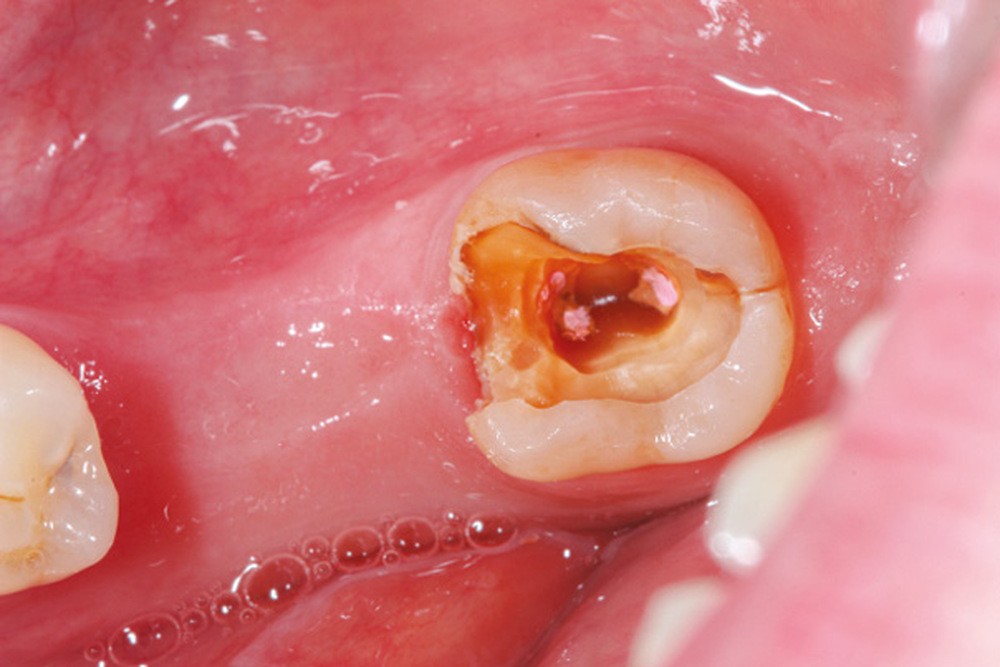

La répartition de la charge occlusale sur l’ensemble d’une arcade est aussi perturbée après une ou plusieurs extractions, ce qui peut occasionner des surcharges occlusales pour les dents restantes. Selon le délabrement coronaire de la dent [10], une fracture coronaire amélo-dentinaire ou corono-radiculaire peut intervenir sous cette surcharge occlusale et engager le pronostic de la dent concernée (fig. 14 à 17).